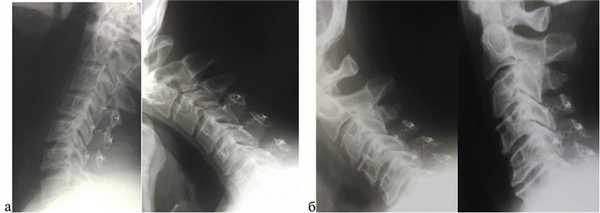

Для исключения сегментарной нестабильности всем больным до операции выполнялось функциональное рентгеновское исследование, в послеоперационном периоде через 3—6 мес выполнялось повторное исследование, не выявившее признаков нестабильности у пациентов нашей группы (рис. 11).

Рис. 11. Пример послеоперационных функциональных рентгенограмм через 16 мес. Признаки сегментарной нестабильности отсутствуют.